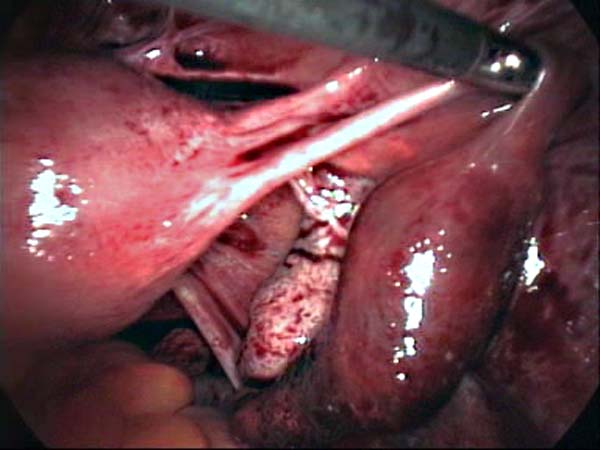

Laparoscopy Photos Ovarian Cyst Ovarian Cystectomy Uterine Septum Tubal Pregnancy